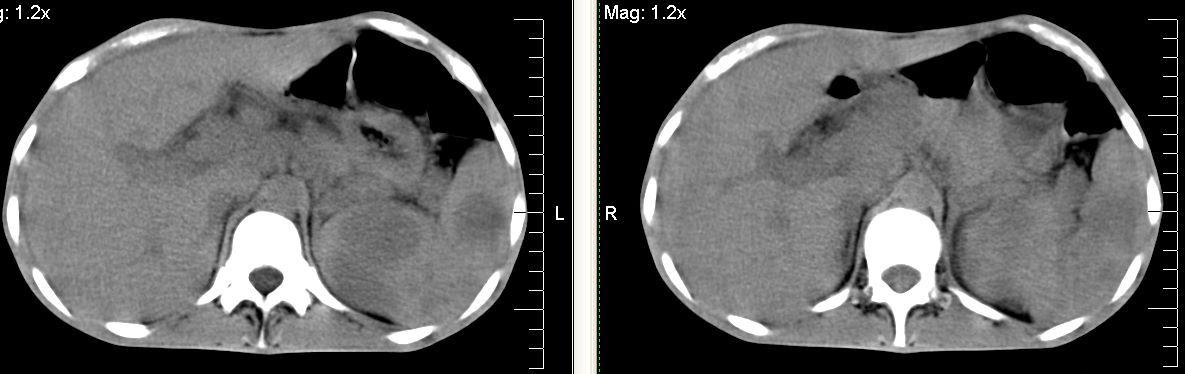

脾脏多发低密度灶,肠系膜及腹膜后见多发大小不等结节状影,右结肠旁沟见低密度影,结合病史考虑:脾结核,肠系膜及腹膜后淋巴结结核,少量腹水。

脾脏多发低密度灶,左侧肾上腺见块状病灶,密度不均,盲肠升结肠肠壁明显增厚,左下腹似可见肠壁增厚,肠系膜及腹膜后见多发大小不等结节状影,右结肠旁沟见低密度影,1淋巴瘤可能大,2结合病史考虑:脾结核,左侧肾上腺结核,肠系膜及腹膜后淋巴结结核,少量腹水待除外,

左肾上腺肿大及脾脏多发低密度灶腹膜后见多发淋巴结舯大

考虑为肾上腺及脾腹膜后多发转移灶